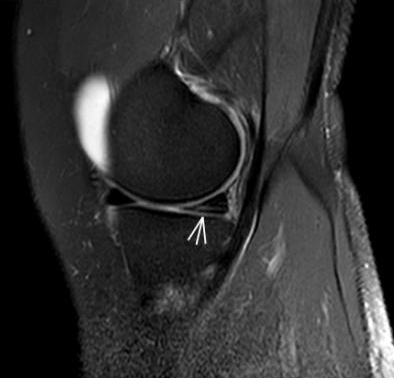

2. 運動后“打軟腿”——韌帶的“斷弦危機”

場景:打球急停后膝蓋不穩(wěn),走路像“踩棉花”

MRI偵查:揪出前交叉韌帶斷裂(呈“波浪狀”或連續(xù)性中斷)、內(nèi)側(cè)副韌帶損傷,防止關(guān)節(jié)“脫軌”

(內(nèi)側(cè)副韌帶損傷)